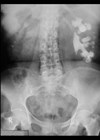

Case 1 A 32-year-old female patient is diagnosed with a ureteric calculus for the first-time. What type of metabolic evaluation investigations should be performed? When should stone analysis be repeated? What are the most common metabolic abnormalities associated with calcium...